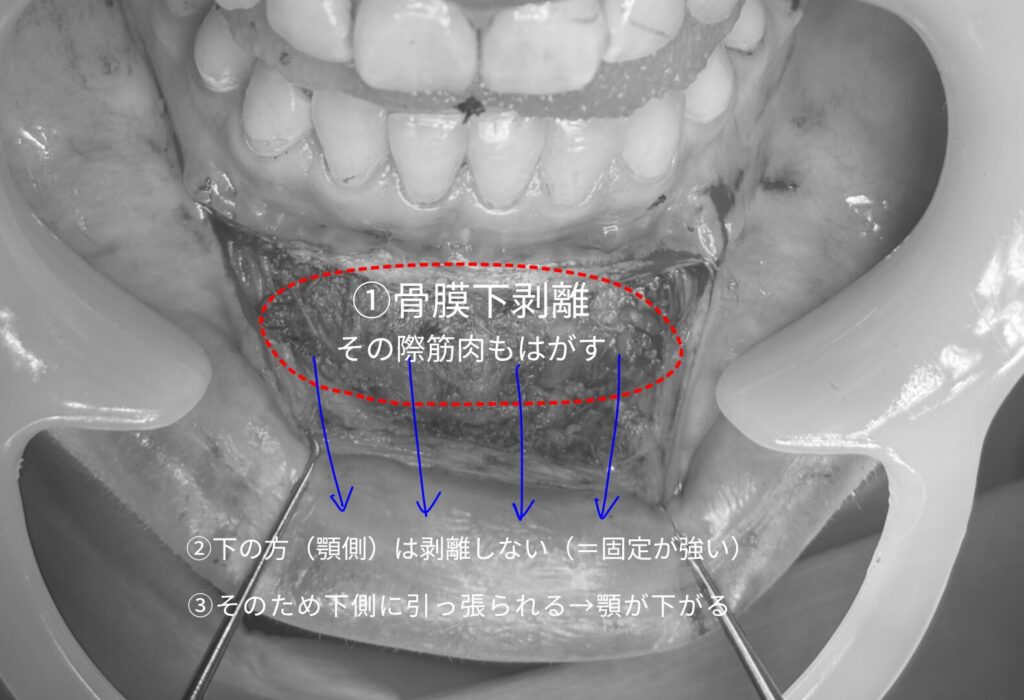

オトガイ形成では、骨の操作を行うために「骨膜」という膜を一度剥がします。

この膜は、筋肉や皮膚を支える大切な構造です。

再癒着が不十分だと、皮膚や筋肉が下方向にずるっと下がってしまいます。

この映像では、上層を剥離すると上が緩み、下方付着が相対的に強くなるという構造を説明しています。

この状態が続くと、笑ったときに顎先が強く引き下げられ、“魔女顎”特有の下垂が起こります。